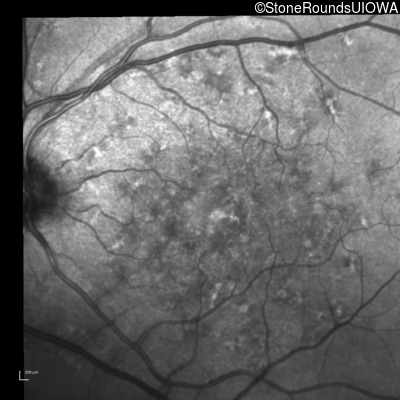

Fluorescein Angiography - Right - 20/250

Exemplar